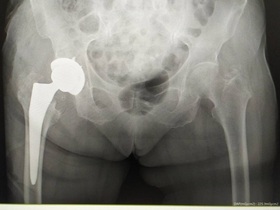

- тотальне ендопротезування кульшового суглоба — операція, у ході якої встановлюється протез, що заміняє всі природні частини суглоба;

- часткове ендопротезування суглоба — встановлення ендопротезу, який заміняє тільки деякі частини суглоба, якщо інші його структури не пошкоджені патологічним процесом або травмою.

Крім того, може проводитися ревізійне ендопротезування кульшового суглоба — хірургічне втручання, під час якого встановлюється новий кульшовий протез замість пошкодженого або зношеного.

Залежно від клінічного випадку лікар обирає спосіб фіксації протезу — цементний, безцементний або змішаний. При заміні кульшового суглоба частіше застосовується безцементна фіксація, застосування цементу більш доречно у випадках, коли у пацієнта спостерігається остеопороз.

Ендопротезування може проводитися під загальним наркозом або із застосуванням епідуральної анестезії. Під час операції хірург робить вертикальний розріз шкіри (його розмір складає приблизно 6-15 см і залежить від обраного типу імпланта). Частини суглоба, які підлягають заміні, видаляються. Замість них встановлюється ендопротез та закріплюється безцементним, цементним або змішаним способом. Хірургічне втручання завершується накладанням швів або скоб та стерильної пов'язки.